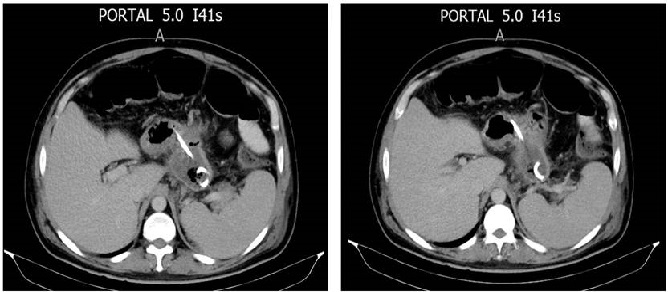

En relación con las características de los pacientes, 5 eran hombres con media de edad de 39 años. Todos los pacientes presentaron NPI como indicación inicial para el drenaje percutáneo. Los abordajes percutáneos para el tratamiento de la NPI fueron el transgástrico, transperitoneal y transretroperitoneal guiado por imágenes, combinándolos dependiendo cada caso clínico (Figura 1 y 2, Tabla 1).

Ahora bien, cuando se escoge el drenaje percutáneo, existen 3 vías posibles para la colocación de los diferentes catéteres: la retroperitoneal, peritoneal y la transvisceral (Figura 4).

Por una parte, este abordaje permite la colocación de uno o más catéteres, lo que posibilita la realización de lavados de la necrosis pancreática a través de los mismos. Estos desbridamientos hidráulicos pueden ser realizados en la cama del paciente sin necesidad de anestesia. Por otra parte, el drenaje percutáneo transgástrico es un procedimiento seguro y efectivo, que no ha presentado complicaciones mayores ni mortalidad en nuestra serie, además de que evita procedimientos mayores, abiertos o laparoscópicos para el tratamiento de la NPI. Esto representa beneficios para el paciente, como lo demuestra el estudio PANTER, en el cual la necrosectomía temprana abierta tiene un índice de morbimortalidad mayor que el step-up approach12.

Actualmente, las prótesis pancreáticas endoscópicas son la primera opción para el tratamiento de la DDP. Sin embargo, el abordaje percutáneo transgástrico podría ser una opción terapéutica, ya que luego de la internalización del catéter, se logra dirigir el líquido pancreático hacia el interior de la cavidad gástrica.